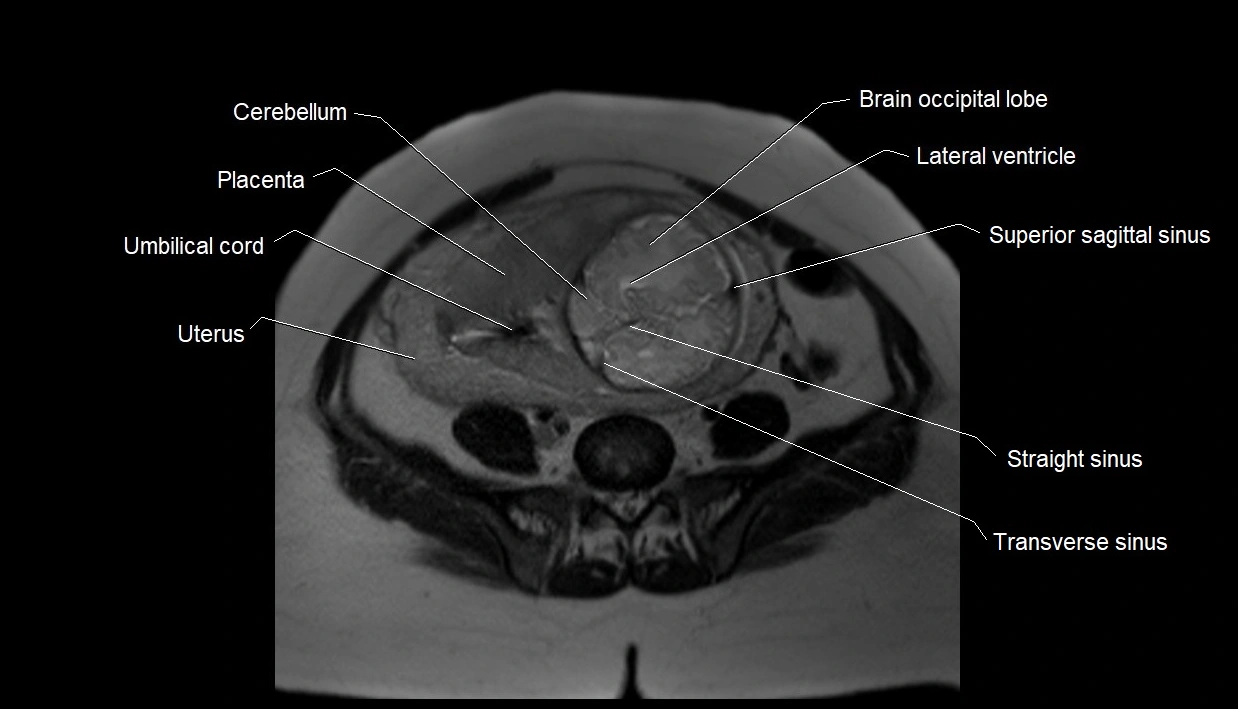

MRI Appearance

T2 HASTE (T2 GRE):

• Amniotic fluid shows very bright hyperintense signal

• Provides natural contrast against fetus and placenta

• Small particles (vernix) may appear as scattered hypointense foci within bright fluid